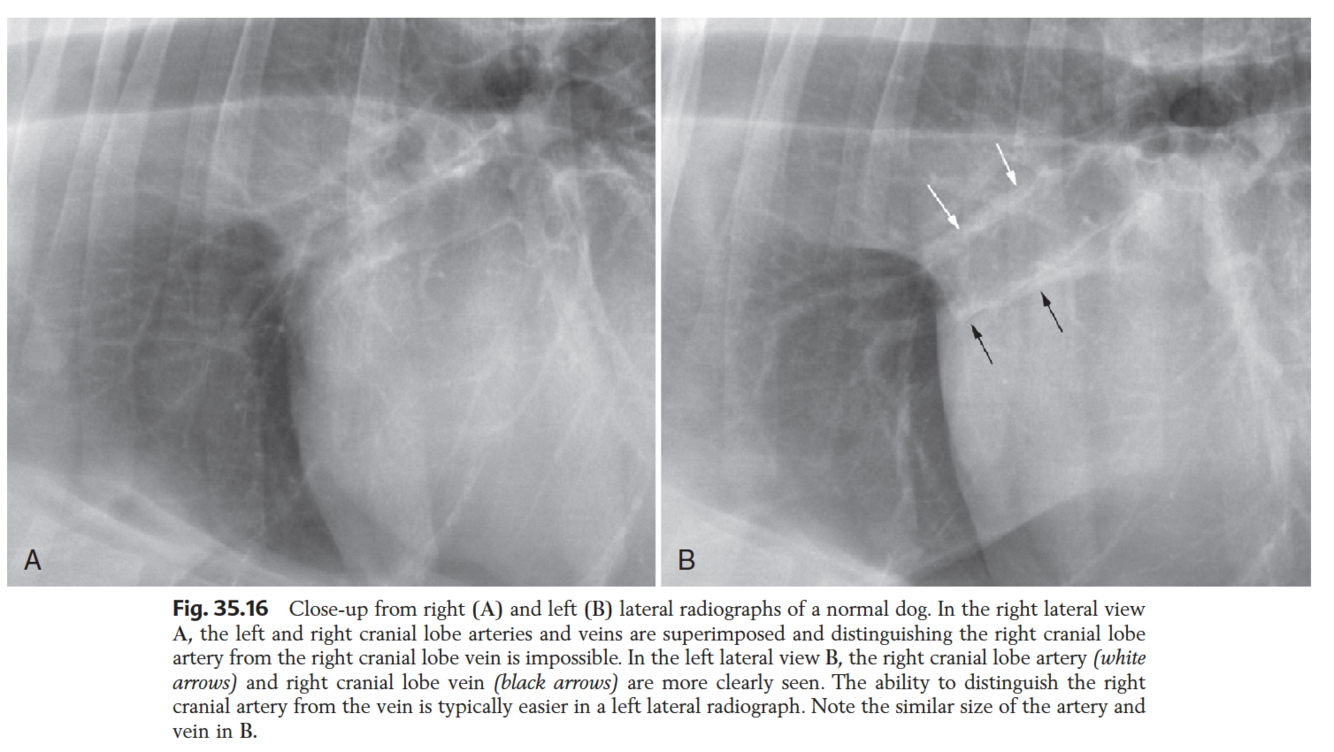

Which projection is best used to evaluate the size of the cranial pulmonary arteries and veins?

LEFT LATERAL

=> in right lateral, often superimposed vessels interfere